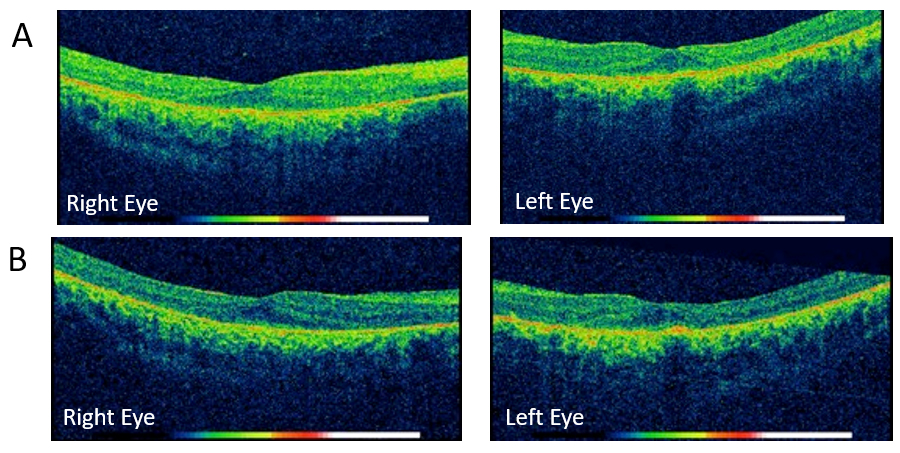

Figure 3. Optic coherence tomography of the individual from Family 1 (II-1). A: The OCT at 8 years of age presented a slight decrease in the macular thickness in both eyes (central macular thickness right

eye: 238 microns/left eye 235 microns) and alteration of the photoreceptor layer. B: OCT at 9 years of age showed a progressive decrease in macular thickness in the left eye.